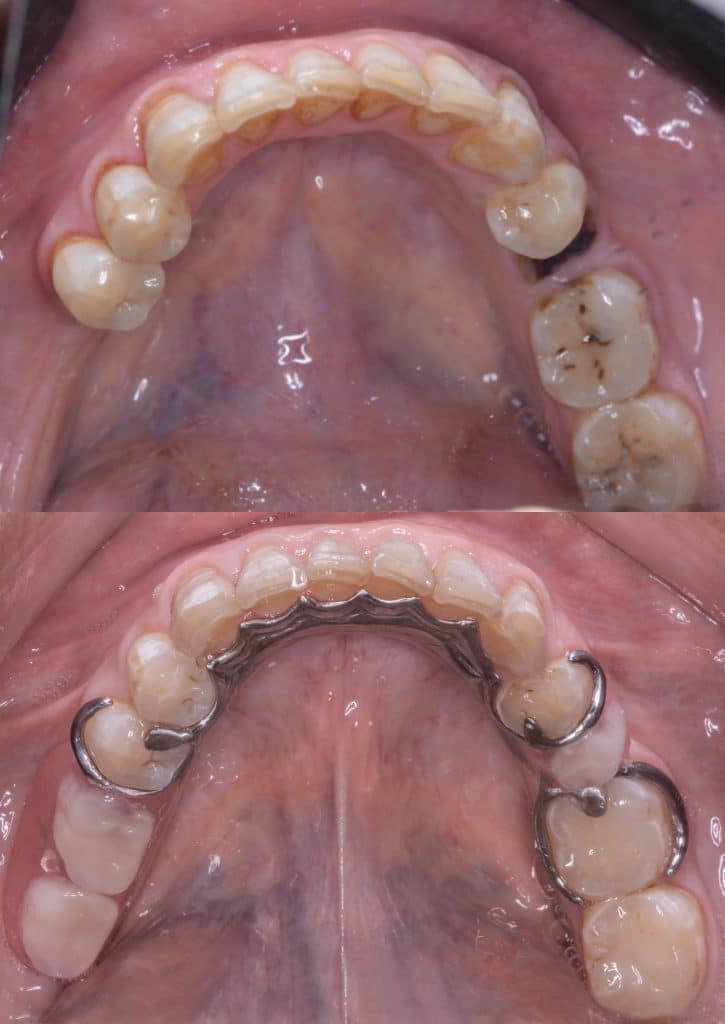

- Preparation of two bridges from 4 to 8 & 9 to 14 with Horizontal prep and subgingival chamfer finish lineNote missing teeth are 6,11,12

- After cementation of the bridges, rest seats were prepared for the RPD

- Metalic Rpd fabricated for class 2 mod 1 kindey classification

All impressions were done using additon silicone putty and wash (Coltene) to ensure good quality of impression and cast and maintain good dimensional stability for long time